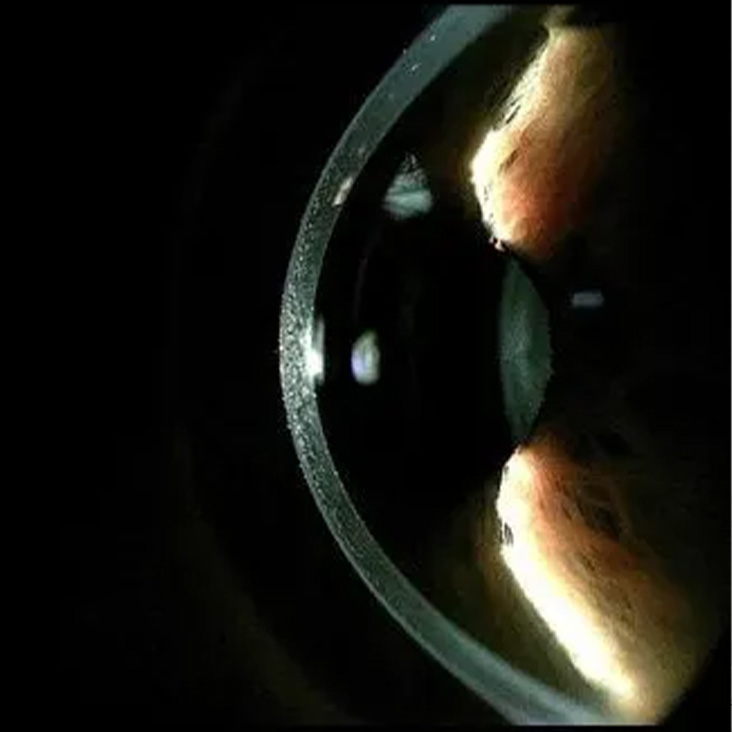

Digital Imaging System

Our advanced equipment allows for high-resolution digital imaging of both the front and back segments of the eye. Utilizing digital photography for documenting your findings

offers several advantages.

It aids in tracking the progression of conditions, enables us to share and securely store images and videos of any pathologies. Furthermore, these captured images

are retained in your records, facilitating the monitoring of changes in your eye health over time.